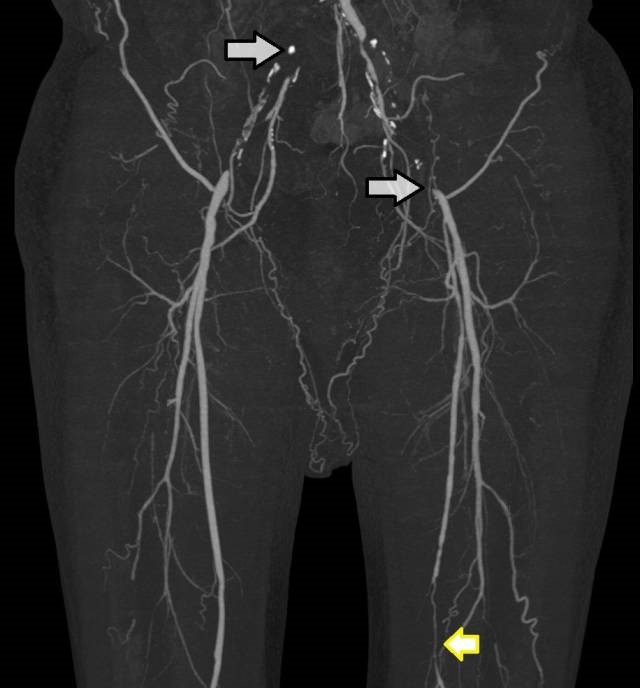

据北大深圳医院微创介入科朱浩医生介绍,下图中白色的管道就是血管,向右箭头显示双侧髂动脉闭塞,向左箭头提示左侧股浅动脉闭塞,血流难以通过,氧气就会供应不足,导致肌肉局部无氧代谢产生酸性物质,所以患者会有疼痛感。而当供血严重不足时,就会出现黄先生这种肌肉发紫发黑的症状。

患者下肢动脉血管CT检查显示图